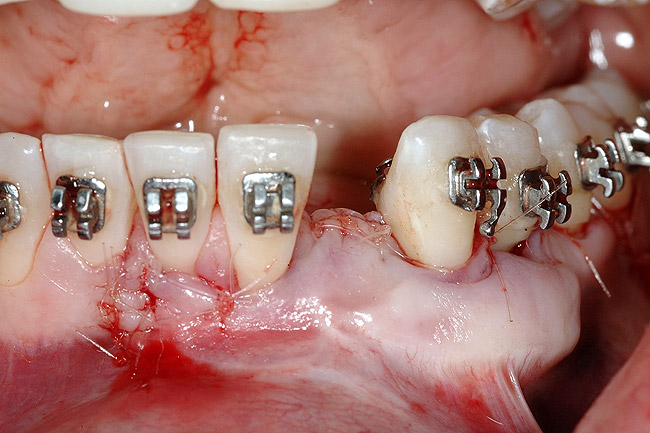

Figure 18  Implant placement with resulting facial dehiscence. Cortical perforations placed to promote angiogenesis.

Figure 18